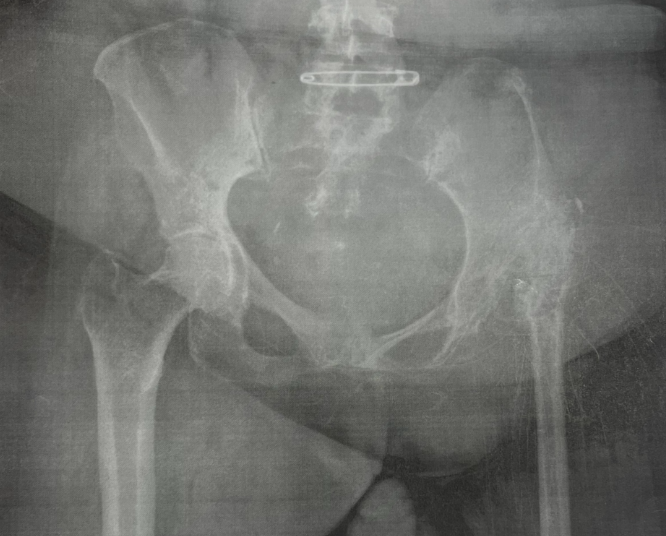

Created OrthoPivot, a custom hip implant designed to address a patient with residual poliomyelitis in the lower limb undergoing total hip arthroplasty.